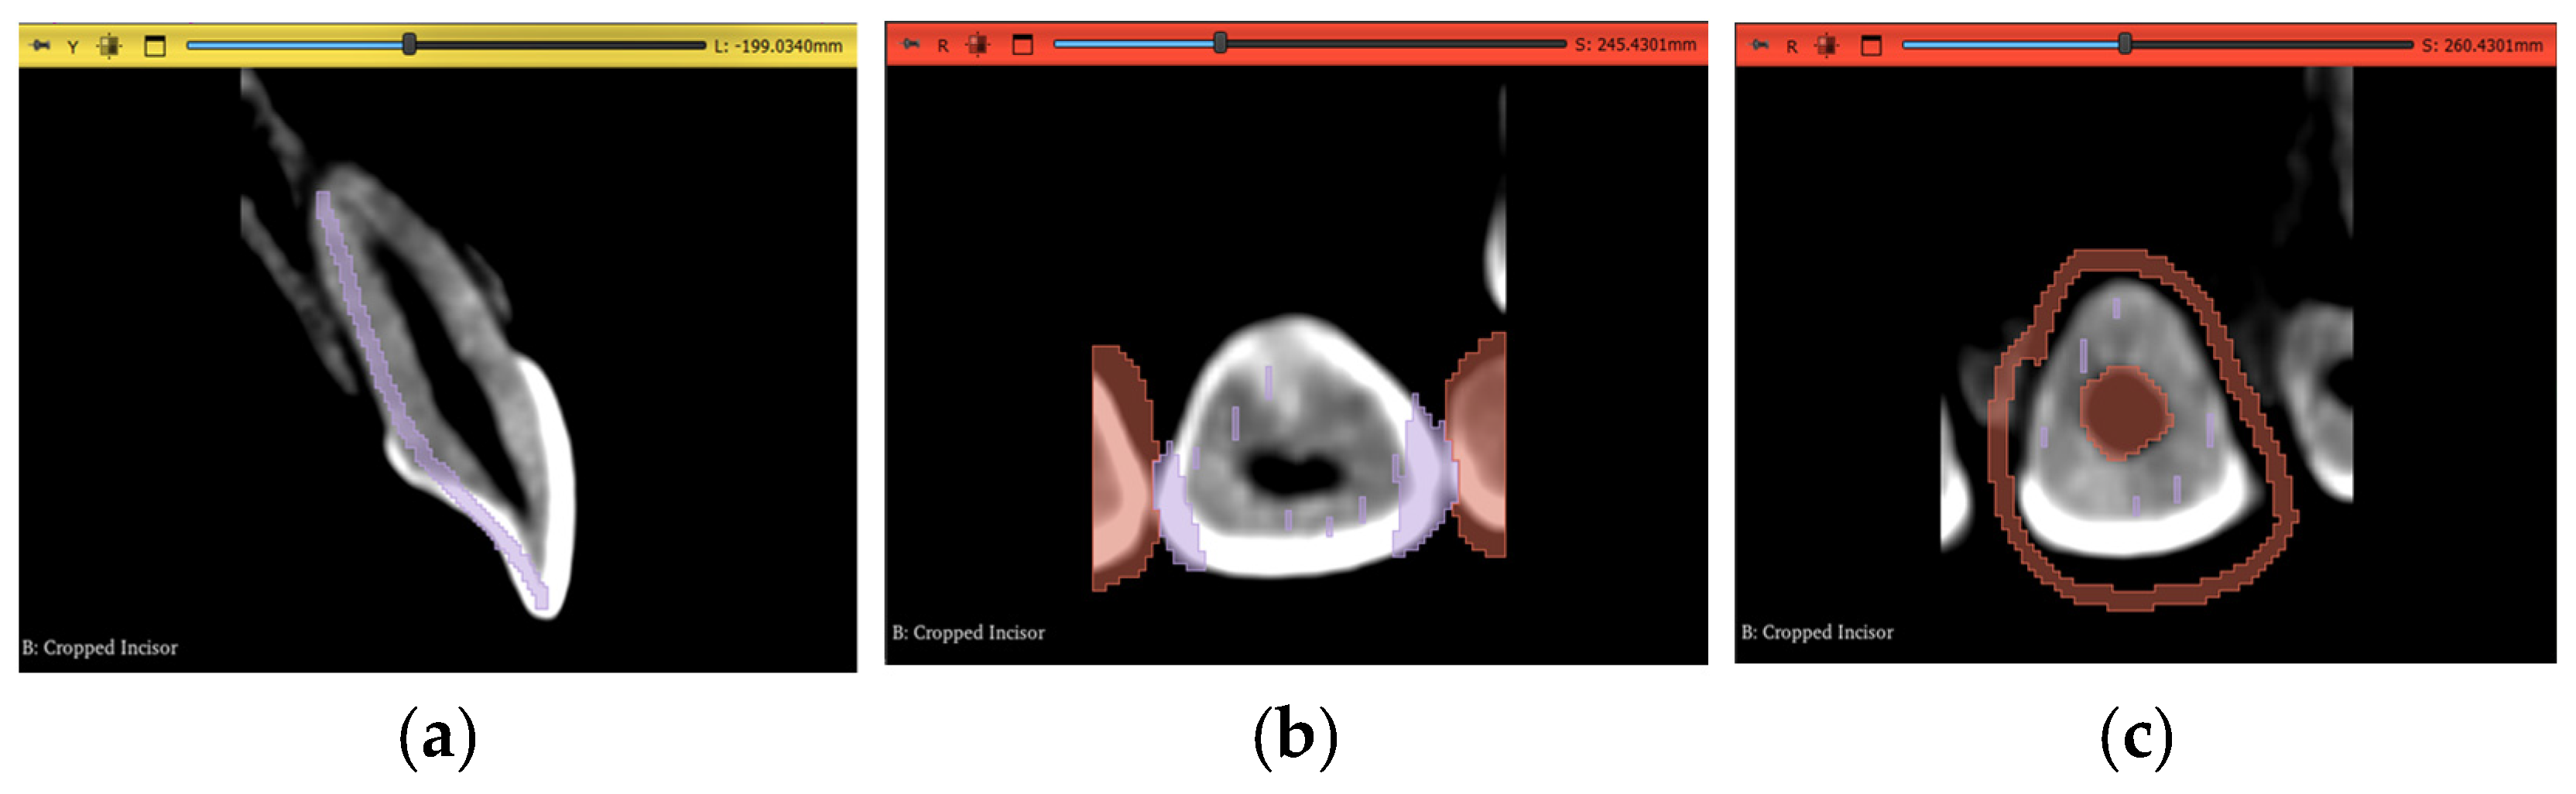

Regarding the actual segmentation procedures, some pre-processing steps were unified and applied to all trials, except the automated method, after importing the datasets, as shown in Figure 7a and Figure 8a, to ensure that any differences were solely due to the actual procedures proposed and not because of any external factors. The pre-processing steps included in the workflow were volume cropping, histogram adjustment, and threshold masking.

Figure 7.

Pre-processing steps performed on the maxillary central incisor of Dataset 1: (a) dataset importing, (b) volume cropping, (c) histogram adjustment, and (d) applying a threshold mask.

2.3.1. Volume Cropping

After importing the dataset, it is convenient to crop the volume to only the area of interest. This is conducted using the “Crop Volume” module in the software. For a completely manual segmentation, cropping the volume is not of much significance; however, it might be quicker and more accurate for other computational approaches to deal with less data and, therefore, it becomes an important step. It is crucial to go through the entirety of the scan in the sagittal, coronal, and transverse planes after bounding the region of interest (ROI) to make sure the intended tooth does not exceed these boundaries and cause a loss of data in subsequent steps. The outcome of this step is shown in Figure 7b and Figure 8b.

2.3.2. Histogram Adjustment

For better differentiation between darker and lighter pixels in the image, a histogram equalization process is one of the solutions. The “Volumes” module in the software is used in this step with the newly cropped volume as its input. Although it is an important step, a histogram that is too narrow will eliminate crucial information from the image. Therefore, the user also must go through the entire three planes during this step to guarantee no valuable pixels have been erased from the scan due to non-uniformity of the tooth density, either within itself or in reference to other teeth. Table 2 shows the values chosen in our specific datasets to adjust the histogram according to the subjective judgment that no valuable information is clipped outside the histogram range, while still offering a cleaner image with less noise than the original dataset. As demonstrated, the numbers will change even inside the same dataset for each ROI, depending on the desired outcome and judgment of the operator.

2.3.3. Thresholding Masking

This step is beneficial to limit the number of errors in consequent steps by using the thresholding tool in the “Segment Editor” module to create a mask of selectable pixels in the image based on the stated brightness level. This is substantially more useful for manual segmentation and iterations of seed correction. The threshold level itself should be selected based on the tooth of interest, as each tooth will have a different range of values. Two segmentation layers are created here, “tooth” and “non-tooth”, to which the mask is applied. The range selected for our datasets are shown in Table 3.

As shown in Table 3, the maximum value of the threshold mask is usually set to the maximum value of the available range, as the enamel part of the tooth most commonly represents the highest value of brightness due to its radiopaque nature. In Dataset 3, however, this is not the case; the brightest pixels are occupied by the metal braces and, therefore, the threshold range is clipped from the dark and bright sides of the scales The masks for the incisor and the molar are shown in Figure 7d and Figure 8d, respectively.

All three pre-processing steps mentioned above will differ in parameter values depending on the subjectivity of the user and how inclusive the output of all necessary data should be. Figure 9a shows a slice of the maxillary second molar in Dataset 2 after the histogram adjustment, with 2 circled areas sharing similar brightness levels. The blue circle is an area of interest belonging to the tooth, while the red circle should not be segmented as part of the tooth. Figure 9b shows how an inclusive threshold minimum value should be selected by accepting the noise caused by the pixels in the red circle to gain selection access to the pixels in the blue circle, and Figure 9c shows a bad example of parameter selection for the threshold range, as part of the tooth is not covered despite the selection seeming cleaner and having less noise. The time taken to review that all operations are satisfactory and will not cause any data loss is around 10 min.

Figure 9.

An example showing the judgment of preprocessing parameter selection: (a) molar before thresholding with red circle showing pixels to be discarded and blue circle showing pixels of interest, (b) conservative and inclusive parameter value of thresholding, and (c) aggressive and exclusive parameter value of thresholding.